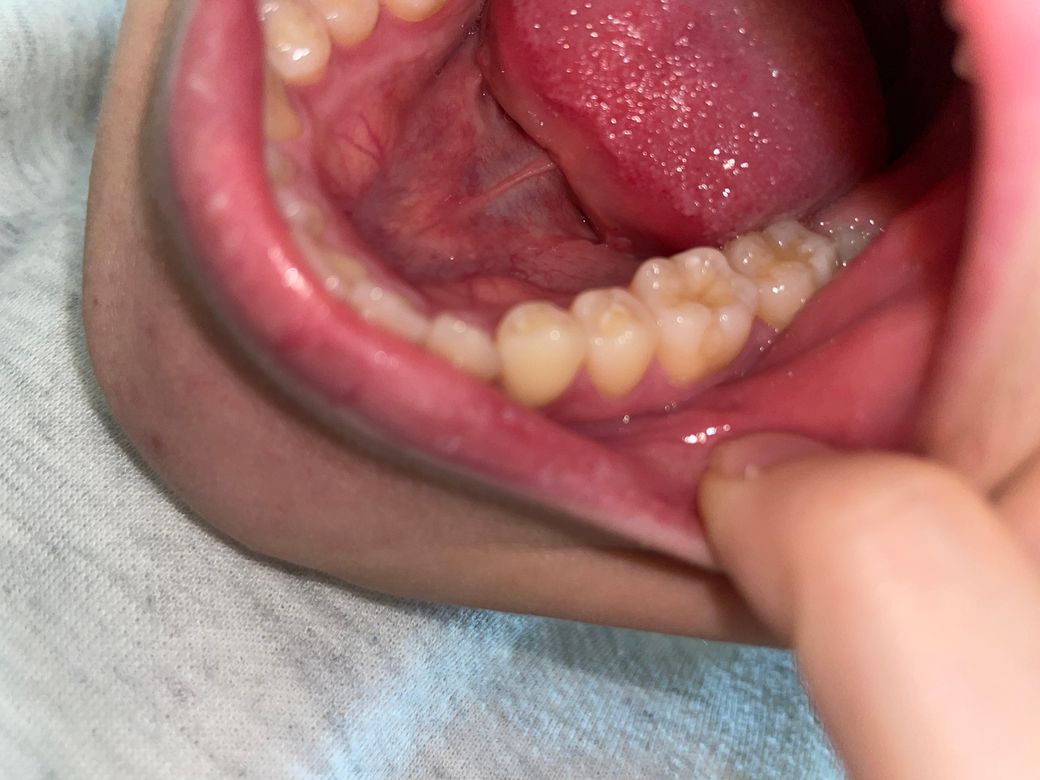

충치일까요?? 구멍은 뭔가요? 치료하려면 많이 아플까요ㅠ

충치일거같긴한데… 구멍도 있는거같아서요ㅠㅠㅠ차가운거 먹었을때만 좀 시려요 ..금데 한 1-2초 후에 바로 괜찮아집니다..!! 근데 제가 치과를 목요일쯤에 갈수있을거같은데 그 사이 더 심해지진 않겠죠 ㅠㅠ? 혹시 이 충치 치료려면 얼마나 아플까요..?ㅠㅠㅠ

어금니에 충치가 보입니다. 따라서 해당 부위의 치료가 필요할 것으로 보이나 현재 차가운것에 시린 증상은 해당 치아로 인한 것인지 다른 치아에도 문제가 있는지는 치과 방문 후 검진을 받아보셔야 합니다. 대부분 충치는 진행속도가 크지 않으므로 단순히 일주일 정도 지나서 치과를 방문하더라도 큰 차이는 없습니다. 물론 가급적이면 빨리 치과를 방문하는 것이 좋습니다.

치료시 마취를 하고 하시면 통증은 없으니 너무 걱정하지 마세요.

충치는 진행이 느리기 때문에 몇달이상 방치하는 경우가 아니면 큰 차이 없습니다.

다음주 목요일에 가셔도 괜찮을것 같습니다.

간단히 떼우는 치료로 가능할수 있습니다.

목요일까지 큰 문제가 발생할것 같지는 않아보입니다.